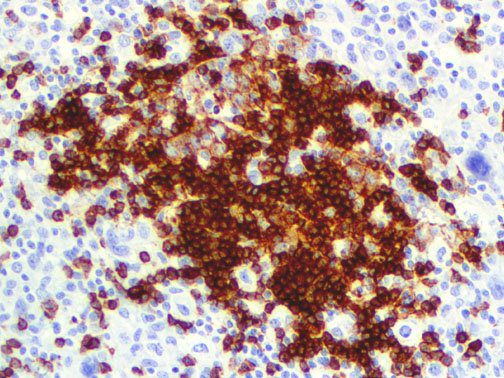

It is the ICU physician who is most likely to witness one of the deadliest manifestations of the abnormal immunological response, the cytokine storm syndrome (CSS). This response is also referred to by some as the cytokine release syndrome (CRS). CSS is characterized by continuous activation and expansion of macrophage and lymphocyte populations, which secrete large amounts of cytokines, causing the cytokine storm. This massive cytokine release is akin to hemophagocytic lymphohistiocytosis (HLH) disease, a syndrome characterized by initial unchecked and persistent activation of cytotoxic T lymphocytes and NK cells.

Clinical and laboratory manifestations of HLH include fever, enlarged liver and/or spleen, neurologic dysfunction, coagulopathy, liver dysfunction, cytopenias (i.e., low levels of erythrocytes, leukocytes, and/or platelets), hypertriglyceridemia, hyperferritinemia, hemophagocytosis, and eventually diminished NK cell activity as the immune system becomes progressively paralyzed. HLH can be familial (primary HLH) or secondary to another disease process (sHLH), such as rheumatic disease, in which it is referred to as macrophage activation syndrome (MAS, characterized by elevated ferritin).